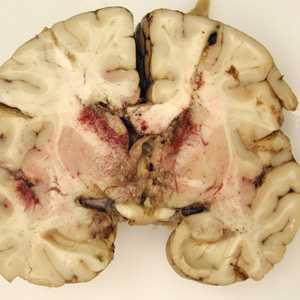

Gross pathology images in free-living amebic infections.

Figure A: Gross specimen of brain tissue from a patient who died of granulomatous amebic encephalitis (GAE) caused by Balamuthia mandrillaris. The autopsy specimen revealed extensive necrotizing (mixed inflammatory, occasional giant cells, vasculitic) granulomatous encephalitis with a subependymal necroinflammatory process. Image courtesy of Cook Children’s Hospital, Fort Worth, Texas.

Figure B: Gross specimen of brain tissue from a patient who died of granulomatous amebic encephalitis (GAE) caused by Balamuthia mandrillaris. The autopsy specimen revealed extensive necrotizing (mixed inflammatory, occasional giant cells, vasculitic) granulomatous encephalitis with a subependymal necroinflammatory process. Image courtesy of Cook Children’s Hospital, Fort Worth, Texas.